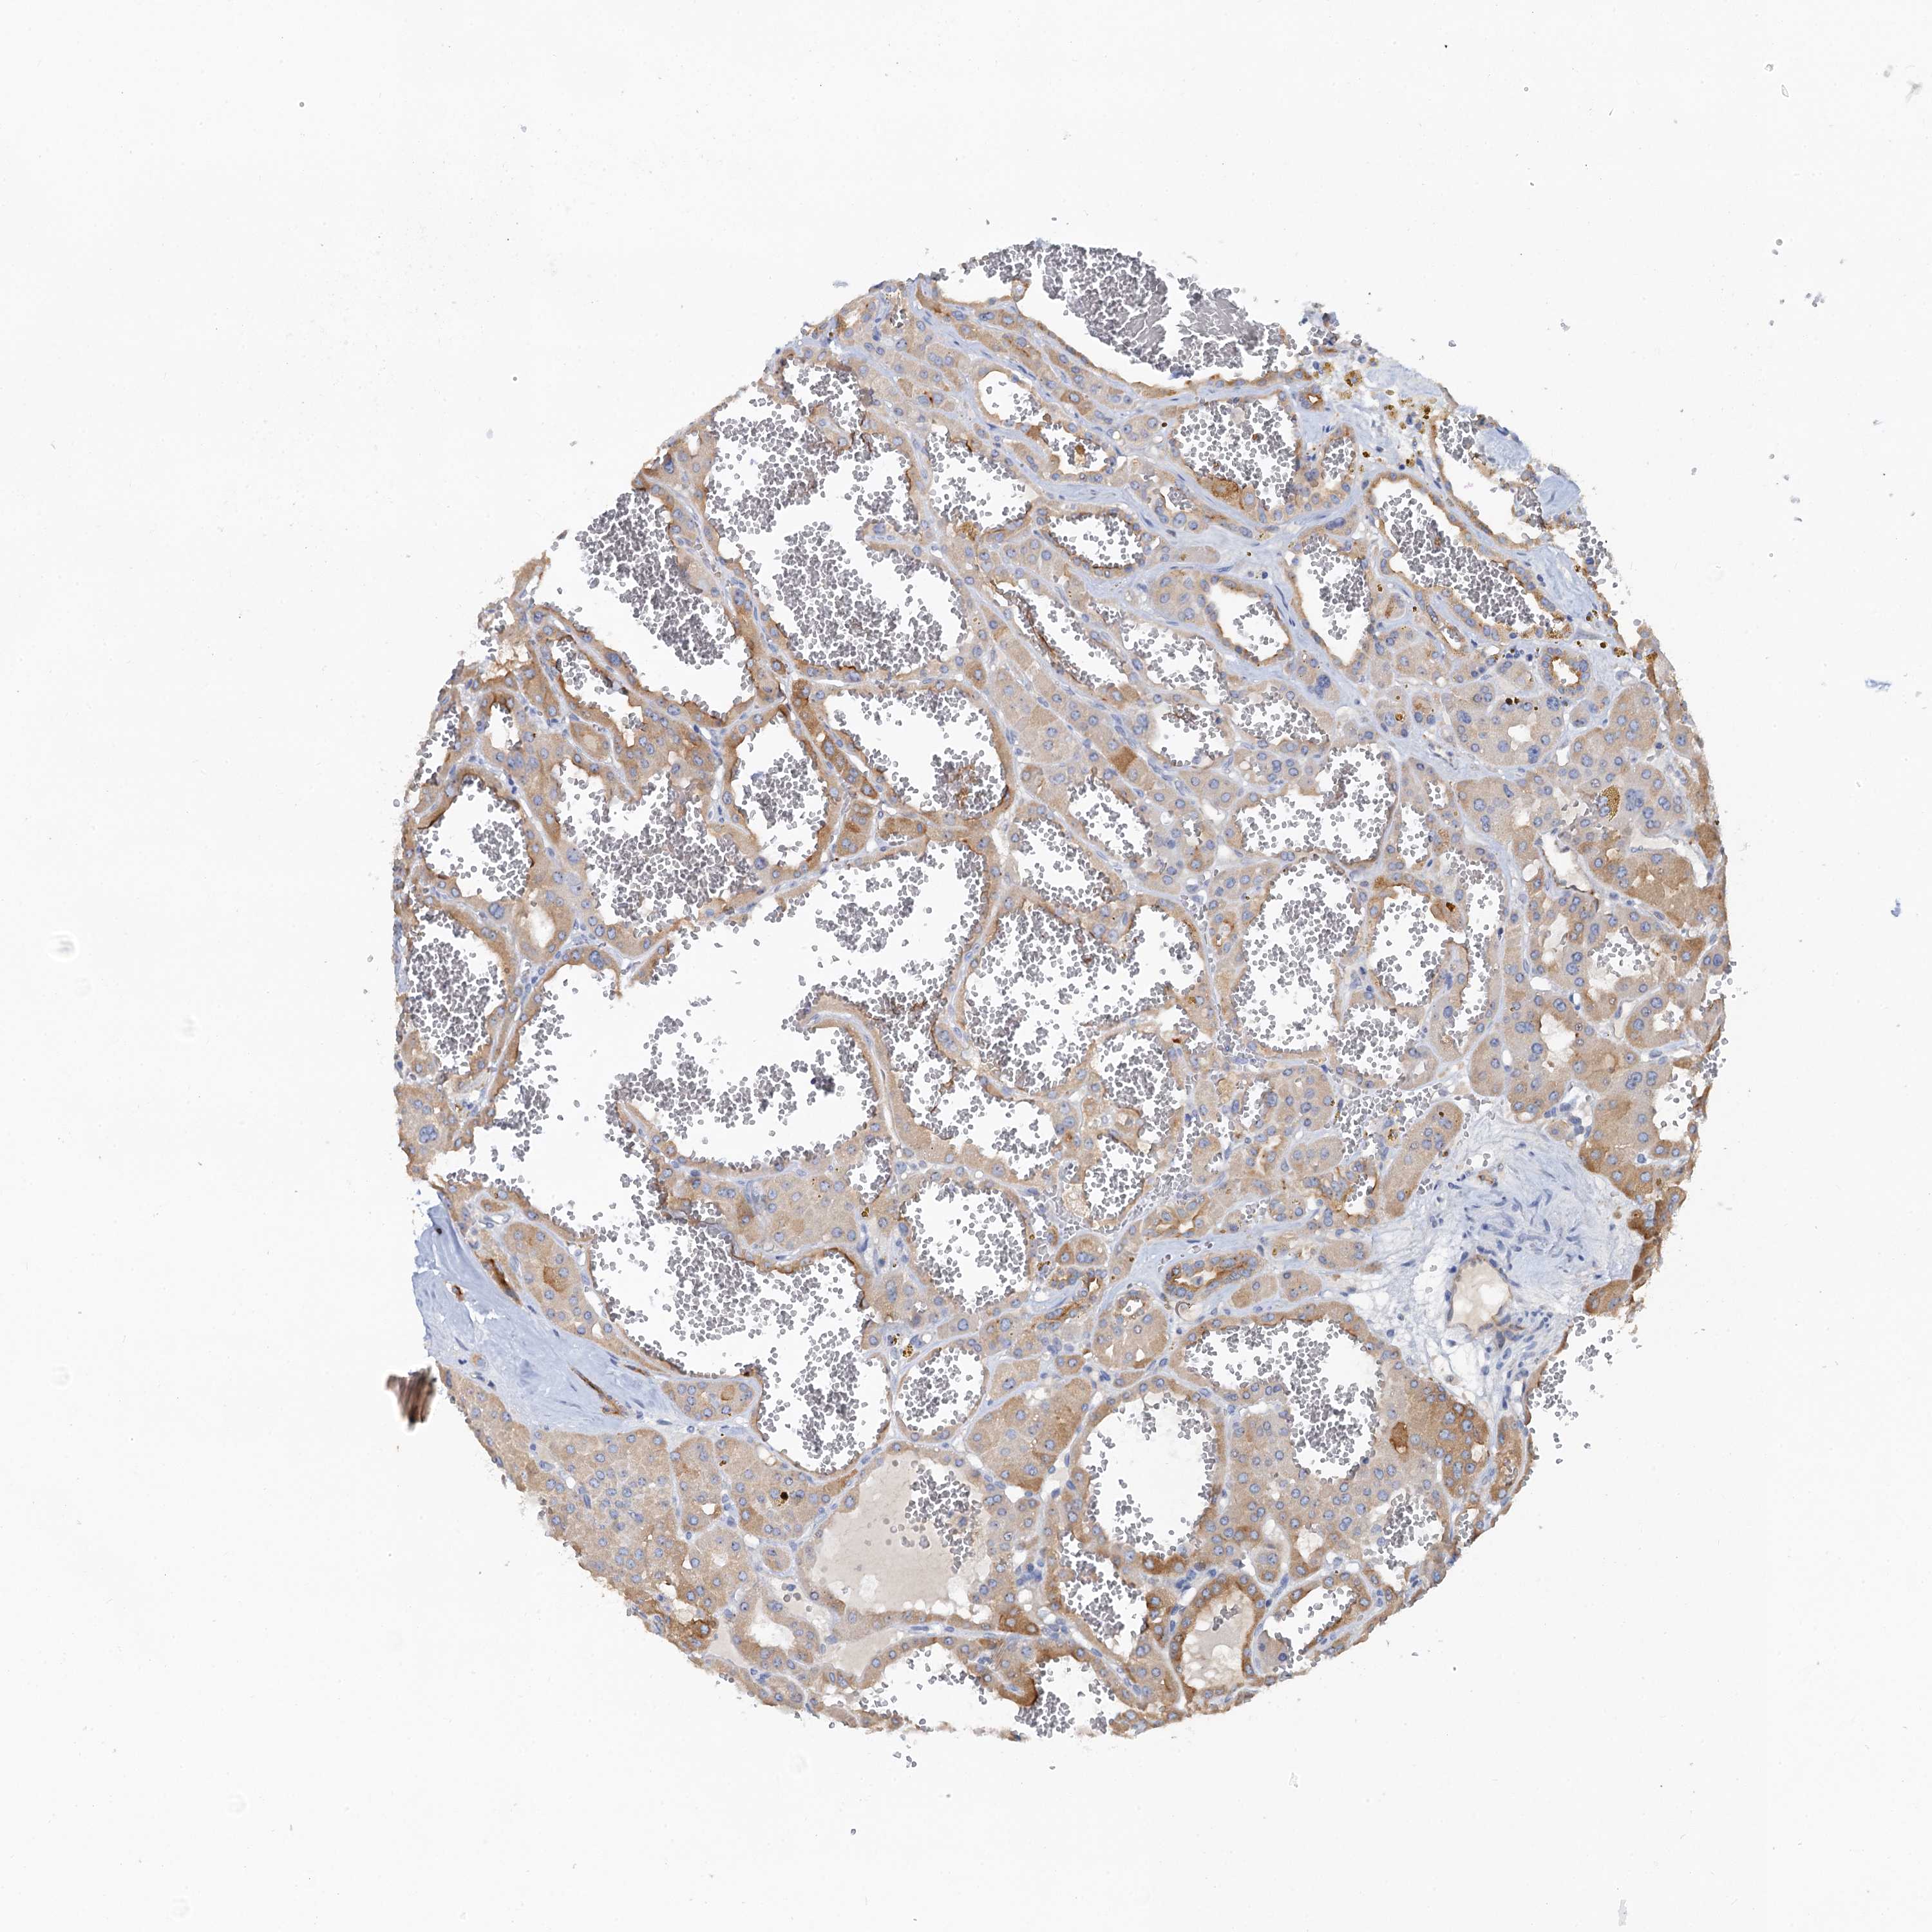

KIDNEY RENAL CLEAR CELL CARCINOMA (VALIDATION) - Interactive survival scatter ploti

The Survival Scatter plot shows the clinical status (i.e. dead or alive) for all individuals in the patient cohort, based on the same data that underlies the corresponding Kaplan-Meier plots. Patients that are alive at last time for follow-up are shown in blue and patients who have died during the study are shown in red.

The x-axis shows the expression levels (FPKM) of the investigated gene in the tumor tissue at the time of diagnosis. The y-axis shows the follow-up time after diagnosis (years). Both axes are complimented with kernel density curves demonstrating the data density over the axes. The top density plot shows the expression levels (FPKM) distribution among dead (red) and alive patients (blue). The right density plot shows the data density of the survived years of dead patients with high and low expression levels respectively, stratified using the cutoff indicated by the vertical dashed line through the Survival Scatter plot. This cutoff is automatically defined based on the FPKM cutoff that minimizes the p-score. The cutoff can be changed by dragging the vertical line or by entering a cutoff value in the square labeled "Current cut-off".

Under the Survival Scatter plot the p-score landscape (black curve; left axis) is shown together with dead median separation (red curve; right axis). Dead median separation is the difference in median mRNA expression between patients who have died with high and low expression, respectively. It is calculated as follows: median FPKM expression of dead patients with high expression - median FPKM expression of dead patients with low expression. This is intended to aid the user in visually exploring custom cutoffs and the associated p-scores and dead median separation.

Individual patient data is displayed and can be filtered by clicking on one or more of the category buttons on the top of the page. Categories describing expression level and patient information include: high, low, alive, dead, female, male and tumor stages. The scale of the x-axis can be toggled between linear and log-scale by clicking on the "x log" button. Mouse-over function shows TCGA ID, patient information and mRNA expression (FPKM) for each patient.

& Survival analysisi

Kaplan-Meier plots summarize results from analysis of correlation between mRNA expression level and patient survival. Patients were divided based on level of expression into one of the two groups "low" (under cut off) or "high" (over cut off). X-axis shows time for survival (years) and y-axis shows the probability of survival, where 1.0 corresponds to 100 percent.

PLLP is validated prognostic, high expression is favorable in Kidney Renal Clear Cell Carcinoma (validation)

Best expression cut offi

Based on the FPKM value of each gene, patients were classified into two groups and association between prognosis (survival) and gene expression (FPKM) was examined. The best expression cut-off refers the FPKM value that yields maximal difference with regard to survival between the two groups at the lowest log-rank P-value. Best expression cut-off was selected based on survival analysis .

When clicking on this number, the vertical dashed line indicating cut-off, the interactive survival plot, and the Kaplan-Meier curve will be adjusted to show results based on the best expression cut-off.

: 10.87

TCGA RNA samplesi

RNA-seq data is reported as average FPKM (number Fragments Per Kilobase of exon per Million reads), generated by the The Cancer Genome Atlas (TCGA) .

Normal distribution across the dataset is visualized with box plots, shown as median and 25th and 75th percentiles. Points are displayed as outliers if they are above or below 1.5 times the interquartile range. FPKM values of the individual samples are presented next to the box plot.

Average pTPM 25.4

Number of samples 100